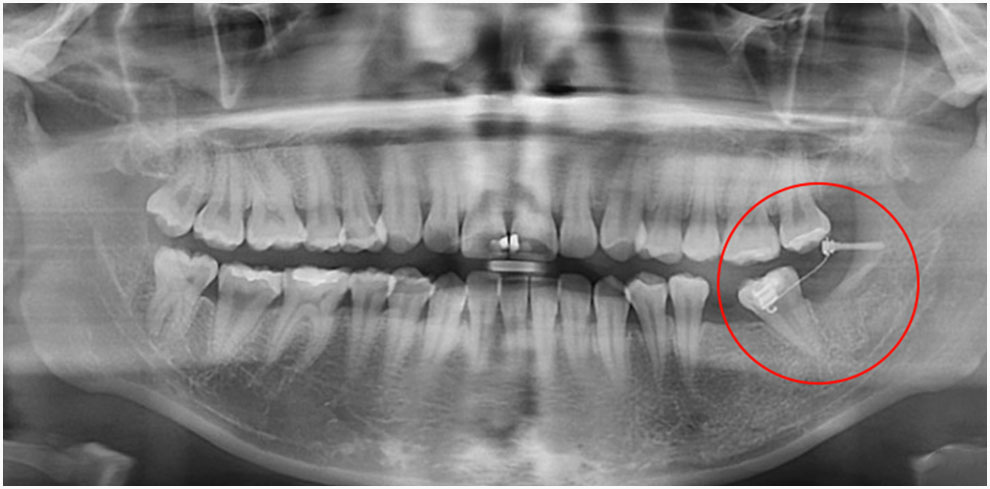

예를 들어, 어금니를 충치로 인해 잃었음에도 적절한 시기에 보철 치료나 임플란트를 하지 않고 방치한 사례가 종종 있습니다.

이러한 상황에서는 빈 공간으로 인접한 치아들이 기울어지거나, 반대쪽 치아가 점점 내려와 임플란트를 심을 공간이 부족해질 수 있습니다.

이럴 경우, 임플란트교정 을 통해 기울어진 치아를 제자리로 되돌리고 적절한 공간을 만든 뒤 임플란트를 심어야 효과적인 치료가 가능합니다.

- 오랜 기간 치아를 발치한 채로 방치한 경우

교정 치료의 순서 는 기울어진 치아를 올바르게 정렬하거나 임플란트를 심을 공간을 우선 만듭니다.